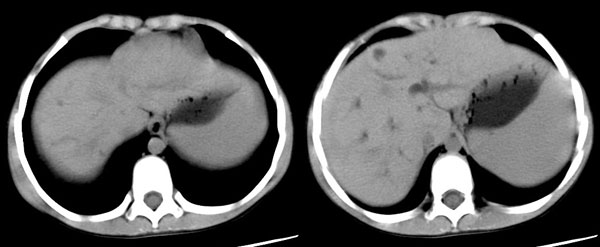

ct平扫:肝脏稍增大,各叶比例在正常范围内,肝左叶见二个小囊肿,直径7mm-10x7mm,余肝实质未见异常密度改变。肝内胆管见轻微扩张,未见钙化结石,胆总管未见扩张。胆囊不大,壁稍增厚,内见一钙化结石达约10x6mm。胰腺形态大小密度正常。脾增大增厚,占8个肋单元,外形光整,密度均匀。双肾大小形态正常,密度均匀。腹腔内未见积液。腹膜后未见肿大淋巴结。

ct诊断:1、脾大。

右股动脉穿刺,将导管置入脾动脉远端,造影显示脾明显增大,脾静脉、门静脉未见异常,采用明胶海绵颗粒行脾动脉部分栓塞。

栓塞后造影可见部分脾动脉分支消失,栓塞面积大于50%。